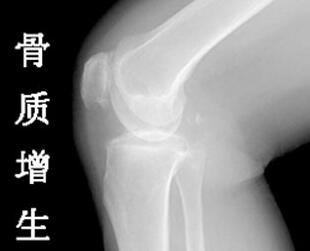

骨质增生患者要如何保养呢

骨质增生患者要如何保养呢?骨质增生患者的保养措施是患者不可忽视的,这是让患者获得更加康复的主要手段,若是患者忽视了,那么疾病的康复将会受到影响,无法得到比较大化的恢复。关于骨质增生的保养可能很多人还不太了解,对此下面杭州江城医院骨科医生就来为大家详细介绍下。